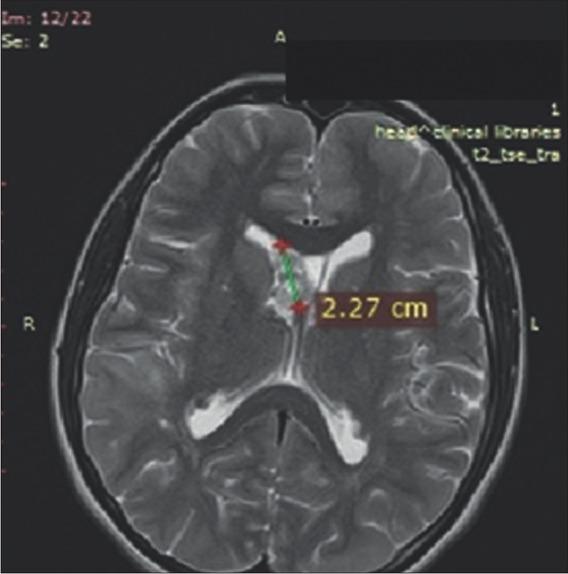

Figure 2

On the brain MRI, multiple lesions as subependimal nodules, subcortical tubers and largest tumor mass presented in foramen Monro as SEGA (diameter 3.0 × 1.5 cm) were described.

Due to the presence of a large brain structural manifestation, continuous follow-up by a neurologist and a neurosurgeon was performed. The majority of TSC patients have neurological symptoms, ~90.0% of affected individuals experience seizures and almost half also experience cognitive impairments, autism, or other behavioral disorders. Epilepsy is seen in 70.0-90.0% of patients, most commonly presenting in the first year of life [12]. Our patient had normal mental status without autism and/or behavioral difficulties. However, seizures were present from the first year of life, with prescribed therapy till 5 years. At the age of 12 years, when the new onset of seizures was registered, an anticonvulsive treatment was reinitiated. After many years free of seizures, the anticonvulsive therapy was again ceased. Thus, after 3 years undergoing everolimus therapy, a new episode of seizure was reported and anticonvulsive therapy was administered. The patient was placed on lamotrigin. The MRI findings excluded hydrocephalus without necessity of surgical treatment. Based on the literature, surgical intervention of SEGA >3 cm has 67.0% risk of surgery-related complications and surgery on tumors >4 cm was associated with 73.0% risk of complications [21,22].

It is recommended that SEGAs are MRI-monitored every 1-3 years in patients younger than 25, as these tumors usually grow in children and young adolescents, but do not have a tendency to grow in adulthood [21,22]. Similar case reports are found in the literature with similar disease presentation and medical treatment [23].